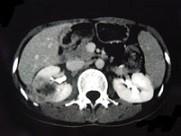

问题 女,33岁,右胁腹痛7天,尿检可见大量的脓细胞,CT平扫+增强如图所示,下列说法正确的是 ( )

选项 A.右肾体积增大,其内可见类圆形低密度病灶 B.增强扫描可见该病灶不均匀强化,其内有无强化的坏死灶 C.右肾病灶边界模糊不清 D.考虑为右肾囊肿合并感染 E.考虑为右肾脓肿

答案 ABCE